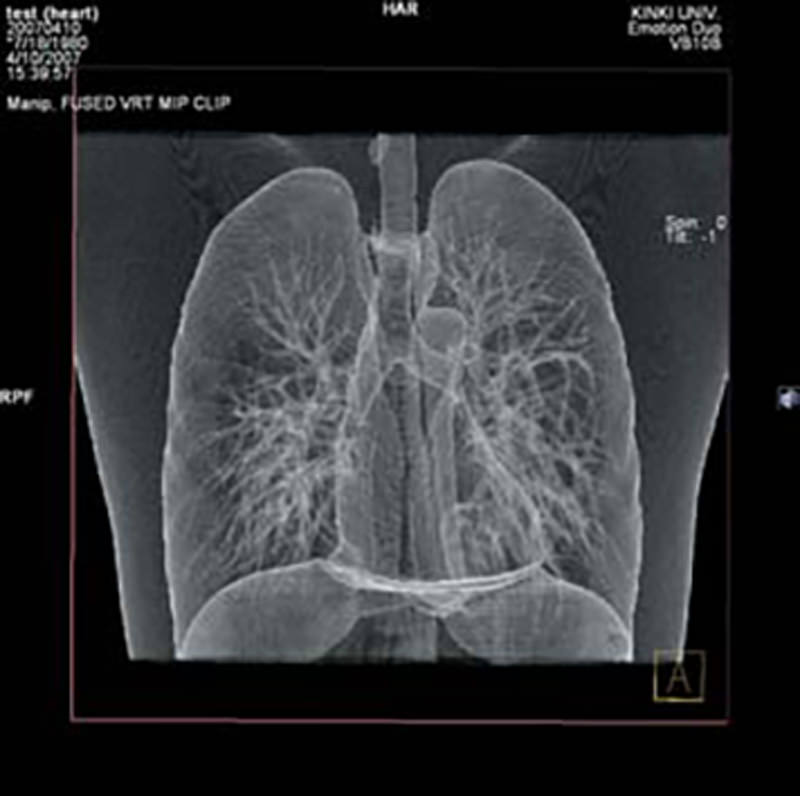

Dieses Vielzweck-Übungsmodell eignet sich für Aufnahmen mit Röntgengeräten und mit Computertomographen. Es eignet sich sowohl zum Erlernen der Aufnahmetechnik als auch für die Ausbildung der Bildinterpretation. Auch für die Gerätewartung und –einstellung eignet sich dieses Modell hervorragend. Die Strukturen des Modells sind aus Materialien mit annähernd natürlichen Röntgenabsorptionswerten gefertigt. Das Model kann geöffnet werden und künstliche Tumore können in die Lunge eingebracht werden. 15 unterschiedliche Tumore werden mitgeliefert.